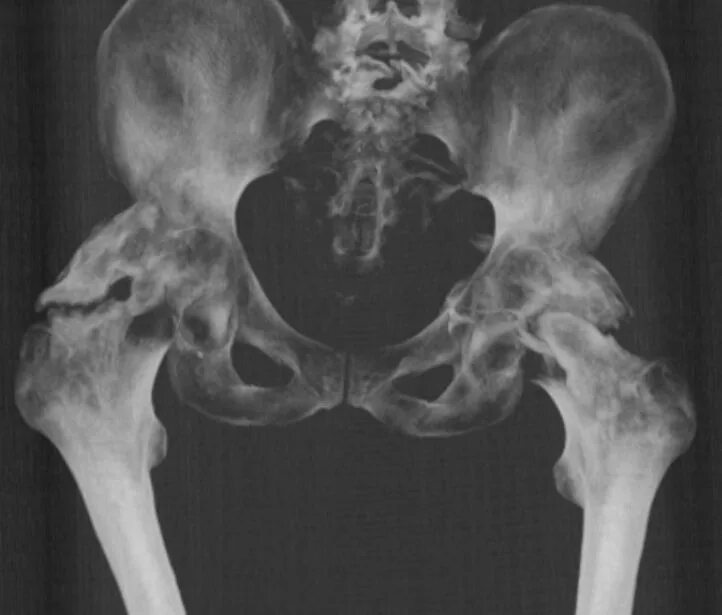

Анкилоз тазобедренного сустава